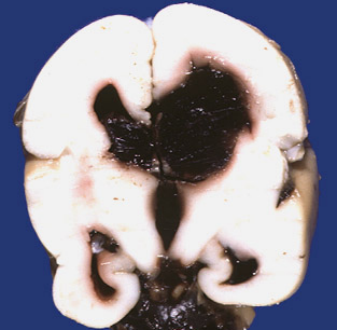

早产儿脑室内出血

生发层基质-脑室内出血

germinal matrix-intraventricular hemorrhage, GM-IVH

脑室周围出血性梗塞

发生率随胎龄降低而增加,在出生体重<1000克或孕周<28周的早产儿IVH患儿中,有15~20%发生出血后梗塞

大多数为单侧,1/2广泛分布于脑室周围白质

与脑室周围白质软化(PVL)的发生常同时存在